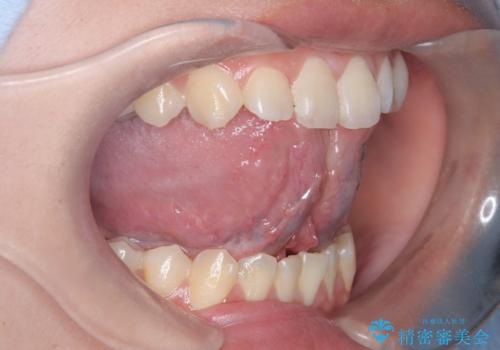

- 「舌が短くて滑舌が悪いので舌小帯を切って欲しい」を主訴に来院された患者様です。

舌小帯切除術を行い舌の可動域を広げ、滑舌の向上を目指しました。

治療後、舌の可動域がかなり広がり患者様に大変ご満足していただけました。